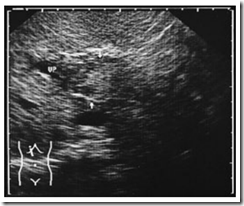

Ultrasound Pictures of  Mesenteric infarction: Segmental thickening of hypoechoic bowel wall (BW) with absence of peristalsis. The bowel lumen appears as an echogenic band

Ultrasound Pictures of  Acute portal vein thrombosis. Mass in the portal vein (VP) is isoechoic to liver tissue (arrows). Doppler scanning shows no evidence of flow.